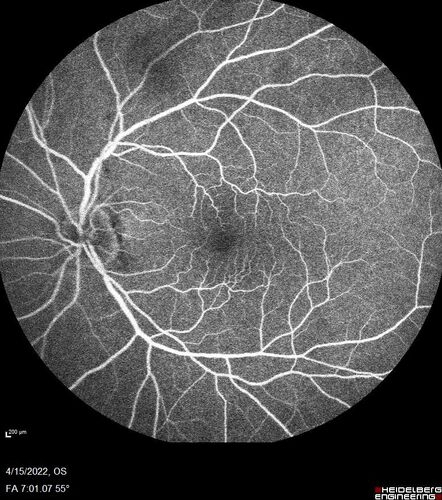

Toxoplasmosis right eye with diffuse retinal vascular whitening PCR confirmed

66 year old man The patient was doing fine until about 2-3 months ago.  He woke up with shadows and spots in the right eye.  Every blue moon he gets some pain in the right eye.  He has been getting treated with eye drops in the right eye.  Since this happened the vision is mostly the same.  Sometimes he sees better than other times.  He has not been treated with oral medications.

Negative labs: ACE, Lysozyme, RPR, HLA B27, Quant TB Gold, ESR (slight elevation of CRP)

PCR anterior chamber: negative herpes virus (HSV, VZV, CMV)

Positive for toxoplasmosis